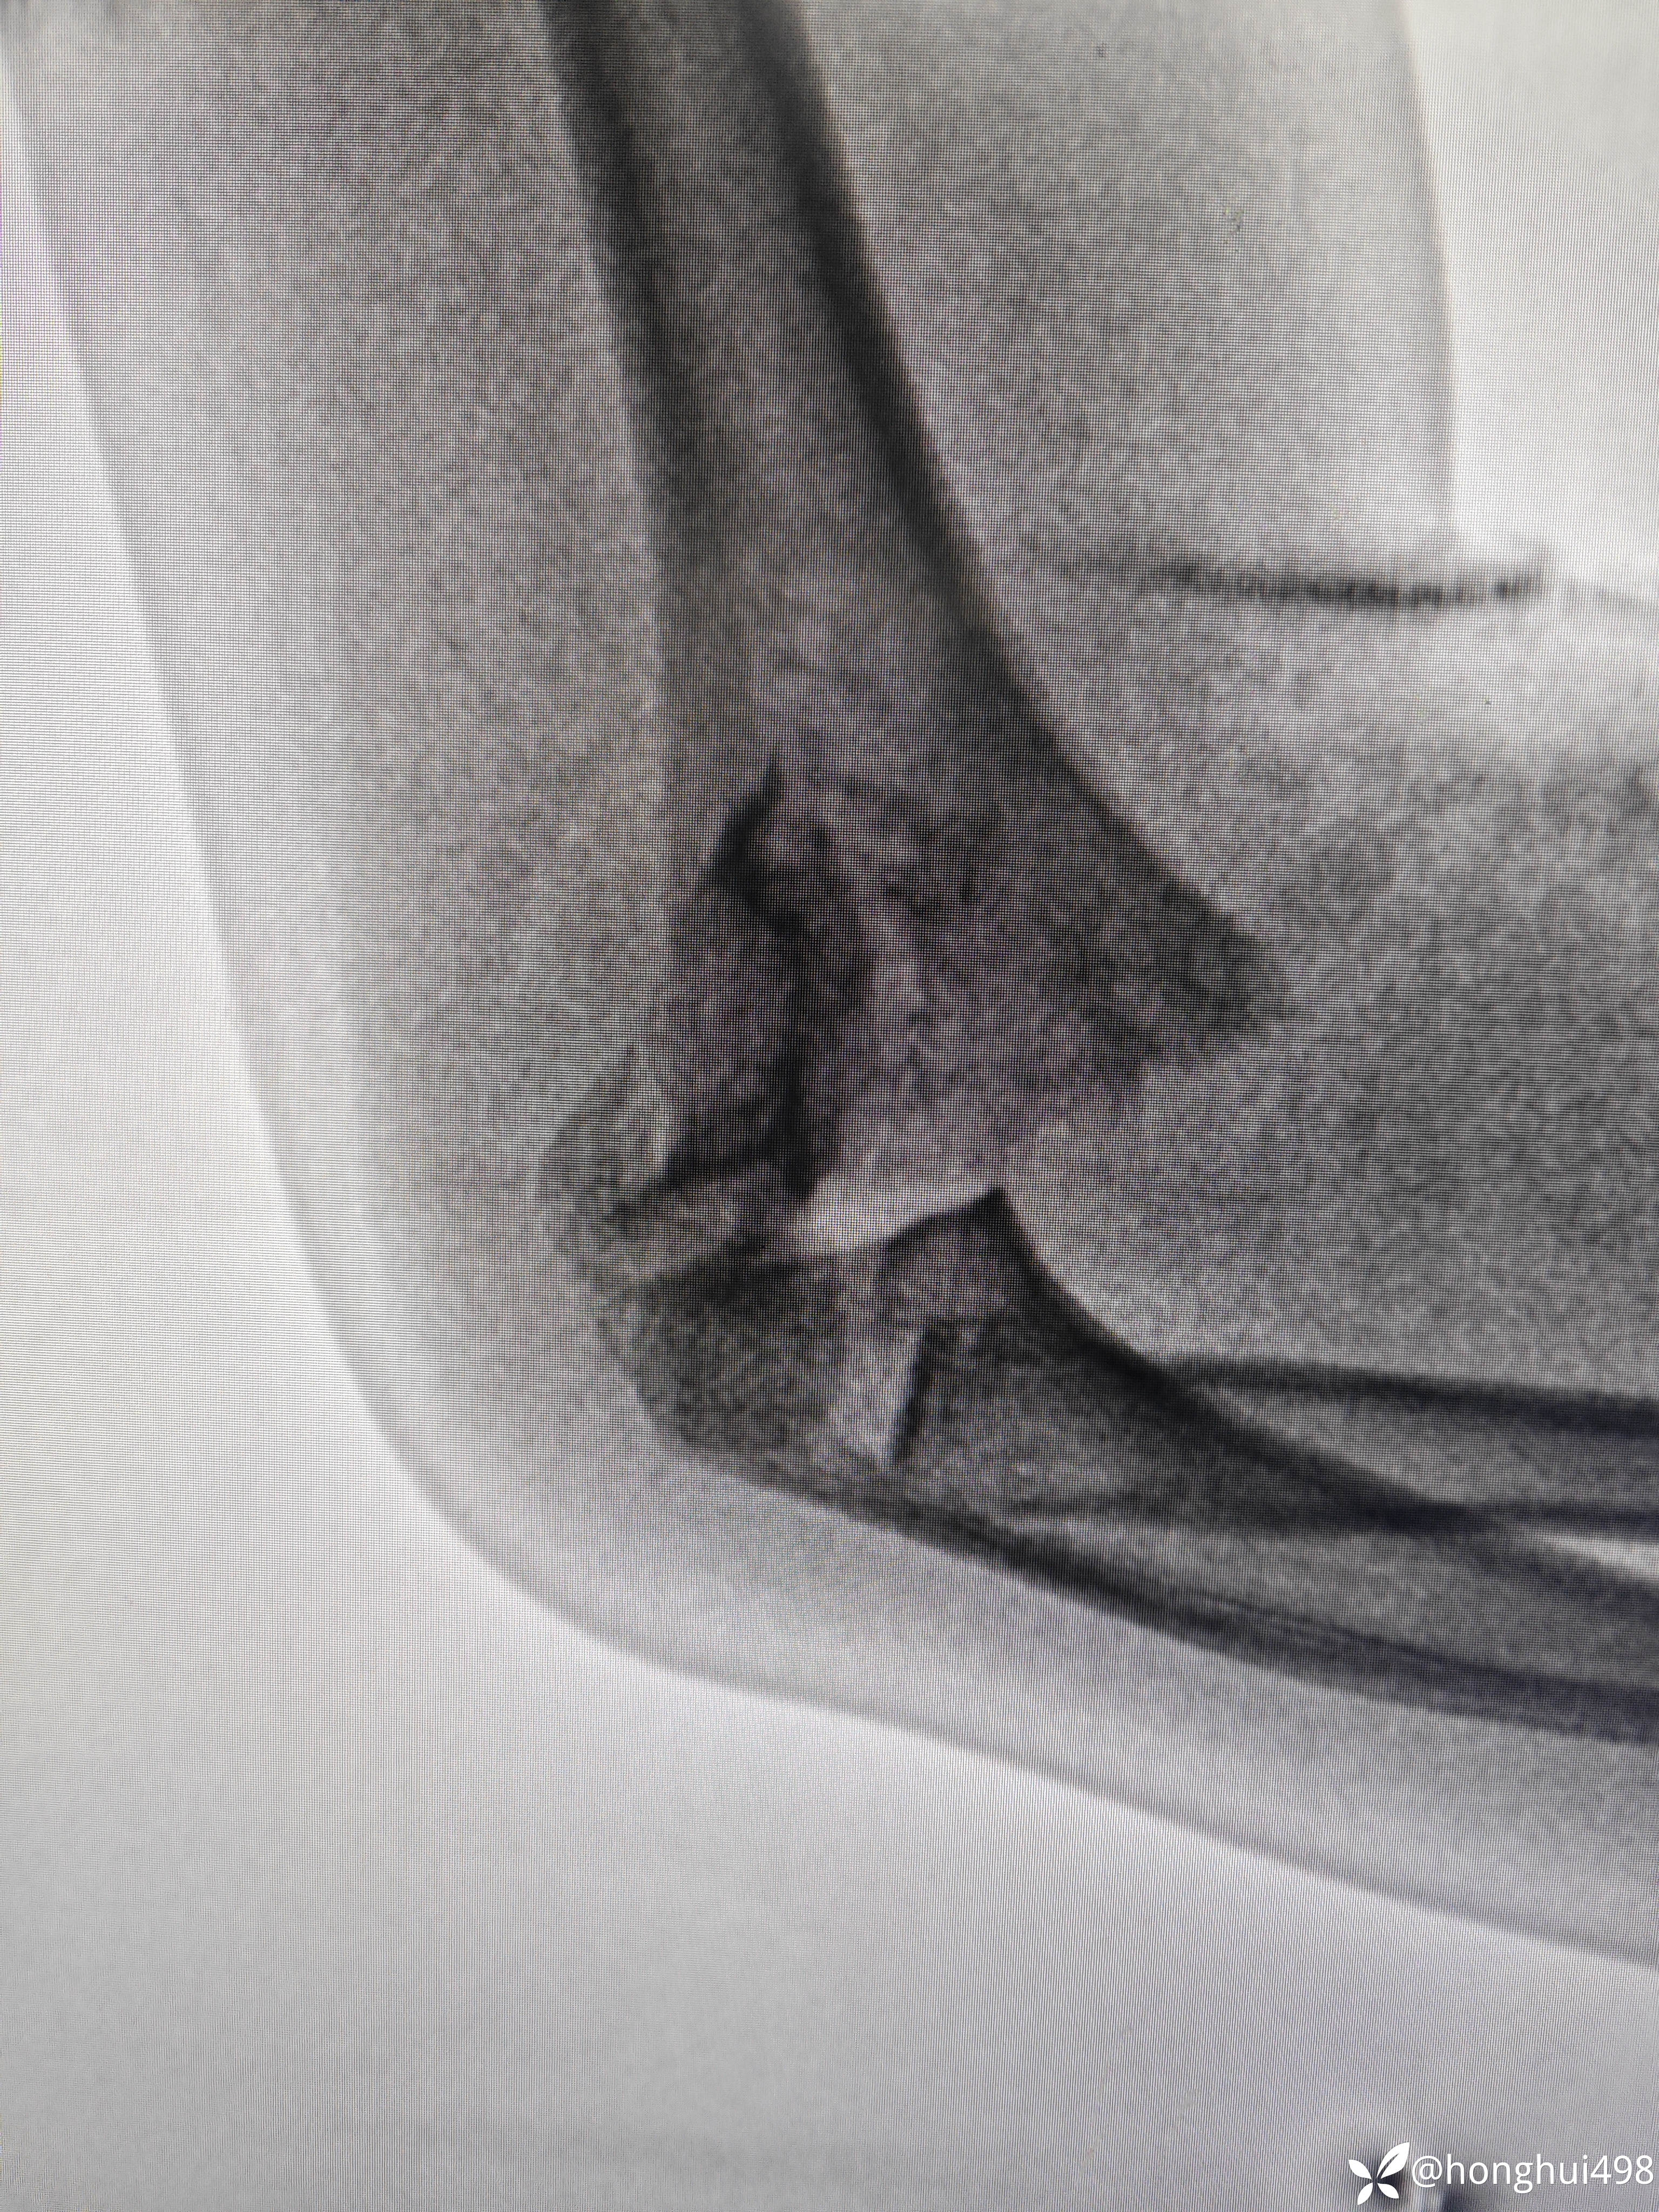

患儿女性,6岁,昨晚8点在家玩耍摔倒受伤,右肱骨髁上骨折。伤后在当地予手法复位草药外敷,伤后15小时来我院就诊,住院麻醉下闭合复位克氏针内固定。